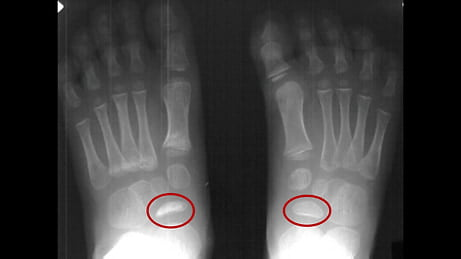

Radiographic Features

In Köhler Disease, the navicular bone typically appears:

- Sclerotic and hyperdense

- Fragmented and small

- Irregular compared to the normal navicular bone

A comparative image may be shown highlighting the difference between normal and necrotic navicular bones.